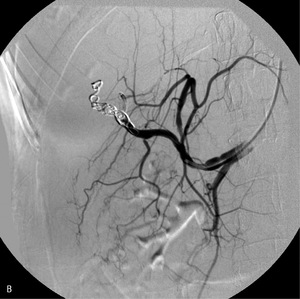

W przewlekłym zapaleniu wątroby najbardziej prawdopodobny jest mechanizm narastania nadciśnienia w wyniku powolnej zaniku drobnych naczyń krążenia wrotnego. W takich warunkach do zakrzepicy jako konsekwencji zwolnienia przepływu dochodzi rzadko – sukcesywnie rozwija się krążenie oboczne, zapewniające odpływ krwi z ominięciem zmienionego narządu. Zakrzepica żyły wrotnej częściej występuje w przebiegu zapalenia trzustki, sepsy, poważnych zaburzeń układu krzepnięcia lub marskości poalkoholowej. W opisanym przypadku przyczyną nadciśnienia wrotnego była pourazowa przetoka tętniczo-wrotna, będąca powikłaniem biopsji gruboigłowej wątroby. Częstość tego powikłania jest większa w przypadku bioptowania marskiego narządu, który jest mniej sprężysty. Przeciek w przetoce narastał powoli, dlatego dopiero po 2 latach przeciążenie objętościowe układu wrotnego spowodowało narastanie żylaków przełyku i krwawienie z górnego odcinka przewodu pokarmowego.